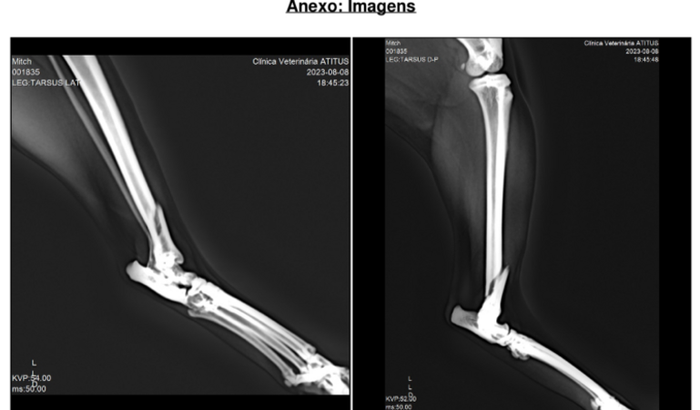

Olá, sou a Larissa, a gatinha da família Miti, nesta terça-feira (08) caiu do telhado de mau jeito e quebrou a patinha traseira. Ela tem cinco anos. Fizemos vários orçamentos e todos o médicos disseram que teria que ser feita a cirurgia, mas o valor de 2540,00 reais, é muito alto pra gente, estamos com outro cachorro idoso em casa com problema na coluna que já gastamos esse valor em remédios e fisioterapia só esse mês! Precisamos de ajuda! Agradeço tua atenção! Meu pix é 09961417909